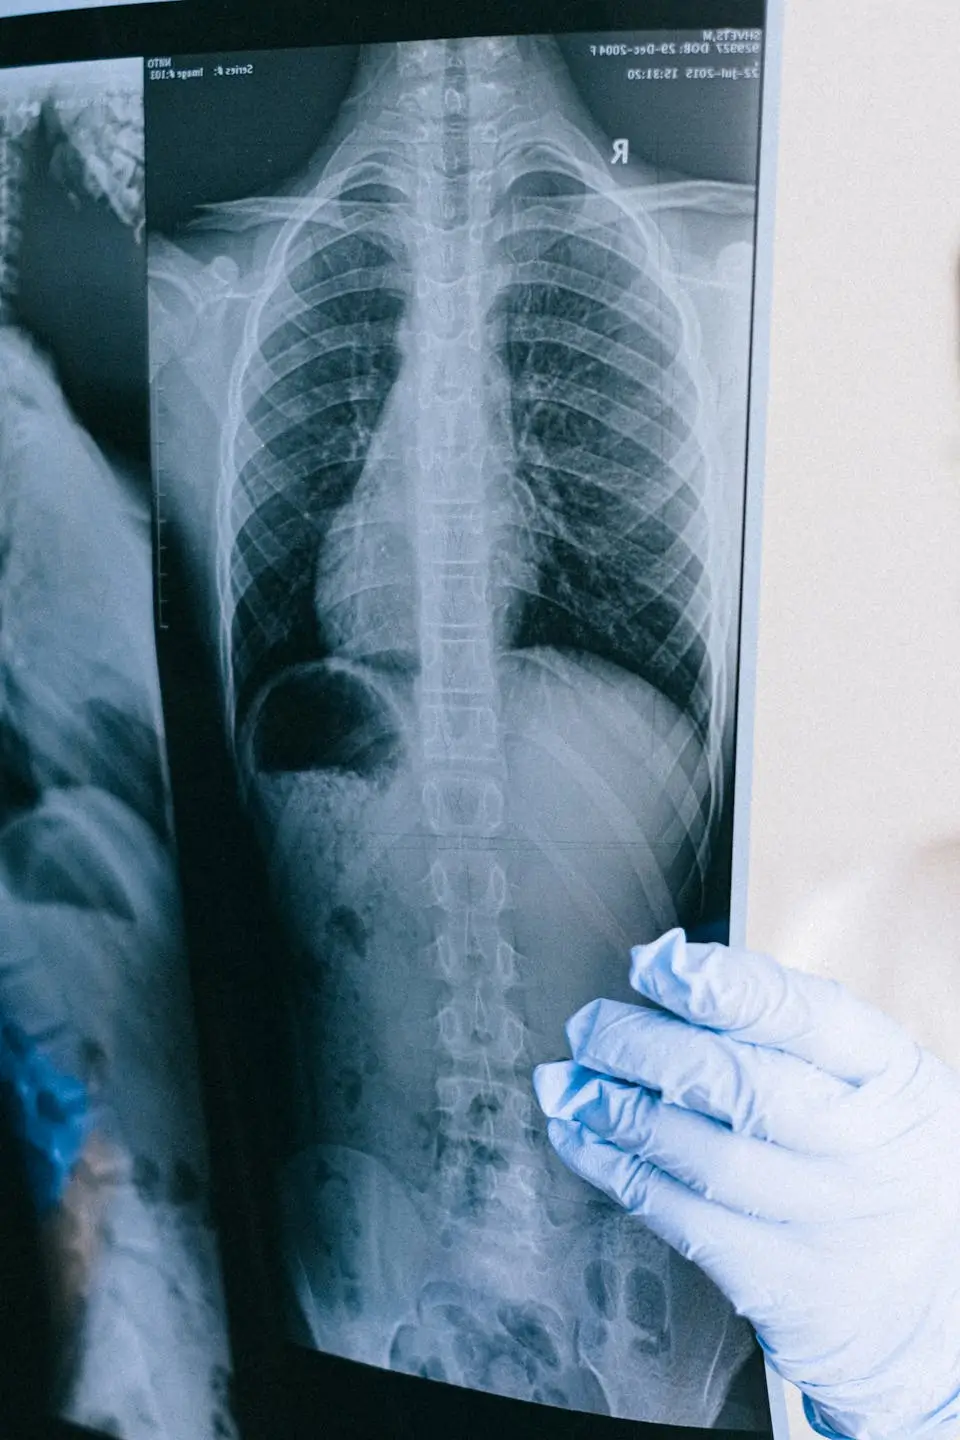

Scoliosis is a structural deformity characterized by a sideways curvature of the spine that can be seen when looking at a person's back. In a healthy spine, the vertebrae are aligned straight and symmetrically; in scoliosis, the spine may show a (C) or (S) shaped curvature. This deformity is not only an aesthetic problem, but also affects the body's biomechanical balance, overall posture, and in advanced stages, the functioning of some internal organs. Scoliosis can be congenital, appear idiopathically during adolescence, or develop in adulthood in a degenerative context. As the angle of curvature increases, the spine's natural range of motion decreases and daily activities become progressively more difficult. Early diagnosis of scoliosis plays an important role in the effectiveness of treatment. Particularly in children and adolescents, as the spine is still growing, the curvature can progress rapidly. In Turkey, the diagnosis and evaluation processes for scoliosis are based on modern imaging techniques and the expertise of spine specialists. In this context, Kanalar Health Tourism contributes to the development of an appropriate and sensitive treatment plan by evaluating scoliosis not only as a spinal deviation but also as a condition that directly affects the patient's quality of life.

Not all scoliosis requires active treatment; however, the severity of the curvature, its potential for progression, and the patient's clinical symptoms are key criteria in making a decision. Mild curvatures can usually be monitored with regular follow-ups and a preventive approach, while scoliosis exceeding a certain angle requires treatment. As the curvature progresses, the balance of the spine is disrupted, leading to asymmetric overloading of the muscles and the onset of back, waist, and neck pain. In young patients, the risk of rapid deterioration during the growth period necessitates early intervention. When treatment is indicated, the evaluation is not limited to measuring the angle of the curvature. The impact of scoliosis on the patient's quality of life is also considered. Difficulty standing for long periods, rapid fatigue, noticeable posture abnormalities, and aesthetic concerns may increase the need for treatment. In advanced cases, deformation of the rib cage can impair respiratory function or lead to neu Canal Health Tourism supports patients during this comprehensive evaluation phase to accurately determine conditions requiring appropriate therapeutic intervention.